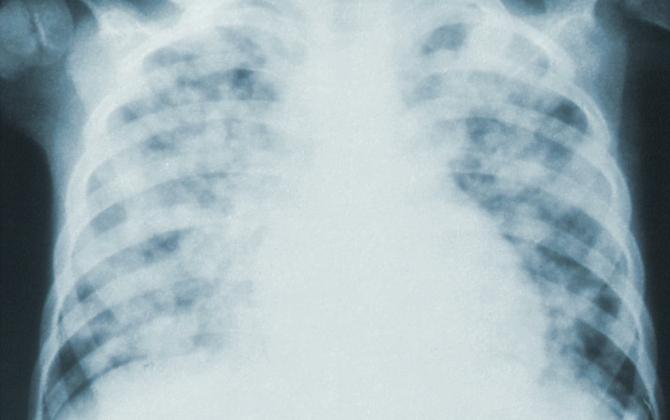

Inspiratory Muscle Training (IMT) has been shown by researchers at NeuRA and Prince of Wales Hospital, to improve lung function by around 30% in people with a spinal cord injury. It may also reduce the risk of chest infections. People who have engaged in inspiratory muscle training programs have reported: IMT improved my strength and awareness of maintaining good breathing habits Gerry After 6 weeks of IMT I had a reduced need for assisted coughs form my carer Will I felt less breathless when sitting upright and could sit for longer Rex IMT makes muscles for breathing stronger and I breathe better Julie Training with the device meant I could talk for longer periods Greg Prince of Wales Hospital and NeuRA have collaborated to develop a COVID-safe protocol for IMT, which has been published by the Agency for Clinical Innovation. It is available here.

Prince of Wales Hospital has funded the development of two training videos to teach people with spinal cord injuries, their carers, therapists, and clinicians how to perform IMT safely and effectively in the community. ParaQuad NSW and Spinal Cord Injuries Australia are two other organisations improving the lives of those with a spinal cord injury by helping to distribute this information. Our aim is to help people take up IMT to reduce the risk of them getting serious lung problems like pneumonia and respiratory failure.